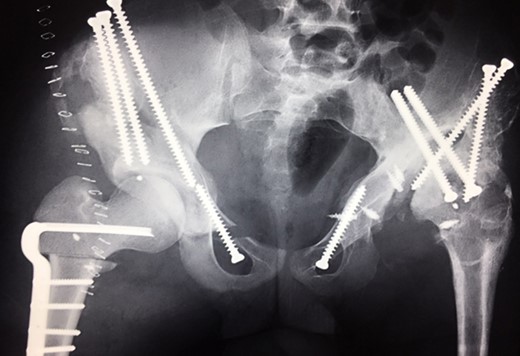

(A + B): (2008) (A) Hip reconstruction with open reduction, Tönnis triple pelvic osteotomy and shortening rotational varus osteotomy of the left femur demonstrating correct deep reposition in ap view. (B) Lauenstein view shows that the acetabular congruency over the femoral head is restored.

Ten years ago, a 12-year-old male presented to our clinic complaining about limping and massive swelling of the left hip. Figure 1 shows the initial X-ray and the 3D reconstruction of the left hip at first presentation when the femoral head, had already destroyed the lateral edge of the acetabulum like a mortar. Severe pain episodes have apparently not been noticed and a former hip dysplasia was not known. A brief clinical history revealed that the patient presented repeated episodes of finger biting and fevers from 2 to 8 years old. The intelligence level of the patient was at an average. The patient was admitted to a paediatric neurologist and a genetic test. A mutation of the NTRK1 gene was found and the diagnosis of CIPA was established. The right hip initially appeared to be normal and the patient was walking, therefore surgical reconstruction for the left hip was proposed due to massive swelling, inability of normal walking and significant limb length discrepancy. A Tönnis/Kalchschmidt triple pelvic osteotomy with open reduction and a shortening varus derotation osteotomy (VDRO) of the femur was performed (Fig. 2A–B). After 3 months the patient was walking again but another 3 months later the hip dislocated again without severe pain. Although the femoral head was already damaged the hip joint was reconstructed again by open reduction, capsular reconstruction with suture anchors and a trevira tube and a movable external fixator was used to temporary stabilize the joint (Fig. 3). The right hip at this time was still intact and was protected with a pneumatic orthotic device. A few months later in 2009, despite all surgeries, the left hip had entirely lost congruency and the right hip developed subluxation despite conservative treatment (Fig. 4). The patient was still walking so the decision to reconstruct the right hip with open reduction, capsular augmentation with a trevira tube, a triple pelvic osteotomy and VDRO was made (Fig. 5). Few months later this reconstruction failed as well and the hip dislocated without severe pain (Fig. 6).